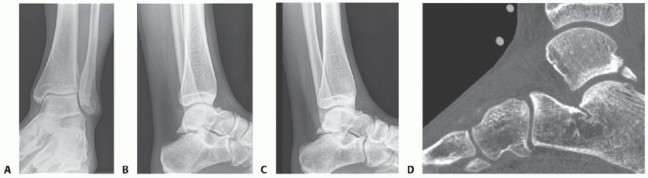

DEFINITION Talus fractures are high-energy fractures that can have traumatic bone loss, avascular necrosis (A…